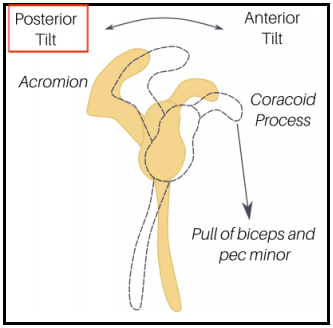

ㆍ앞쪽 기울어짐(Anterior tilting) / 뒤쪽 기울어짐(Posterior tilting)

특히 오훼돌기(Coracoid process)에 붙는 소흉근(Pectoralis minor), 이두근건 장두(Short head Of biceps)의 단축은 견갑골을 위에서 아래로, 앞으로 잡아당기게 되면서 견갑골의 앞쪽 기울임(Anterior tilt)을 유발하며 문제를 일으킬 수 있습니다. 따라서 충격파 치료 시 치료포인트가 이두근의 원위부인 팔꿈치 오목 상부인 이유가 됩니다.

소흉근, 이두근 단두의 단축 -> 앞쪽기울임(Anterior tilting) 상태가 유지 -> 충돌 증가